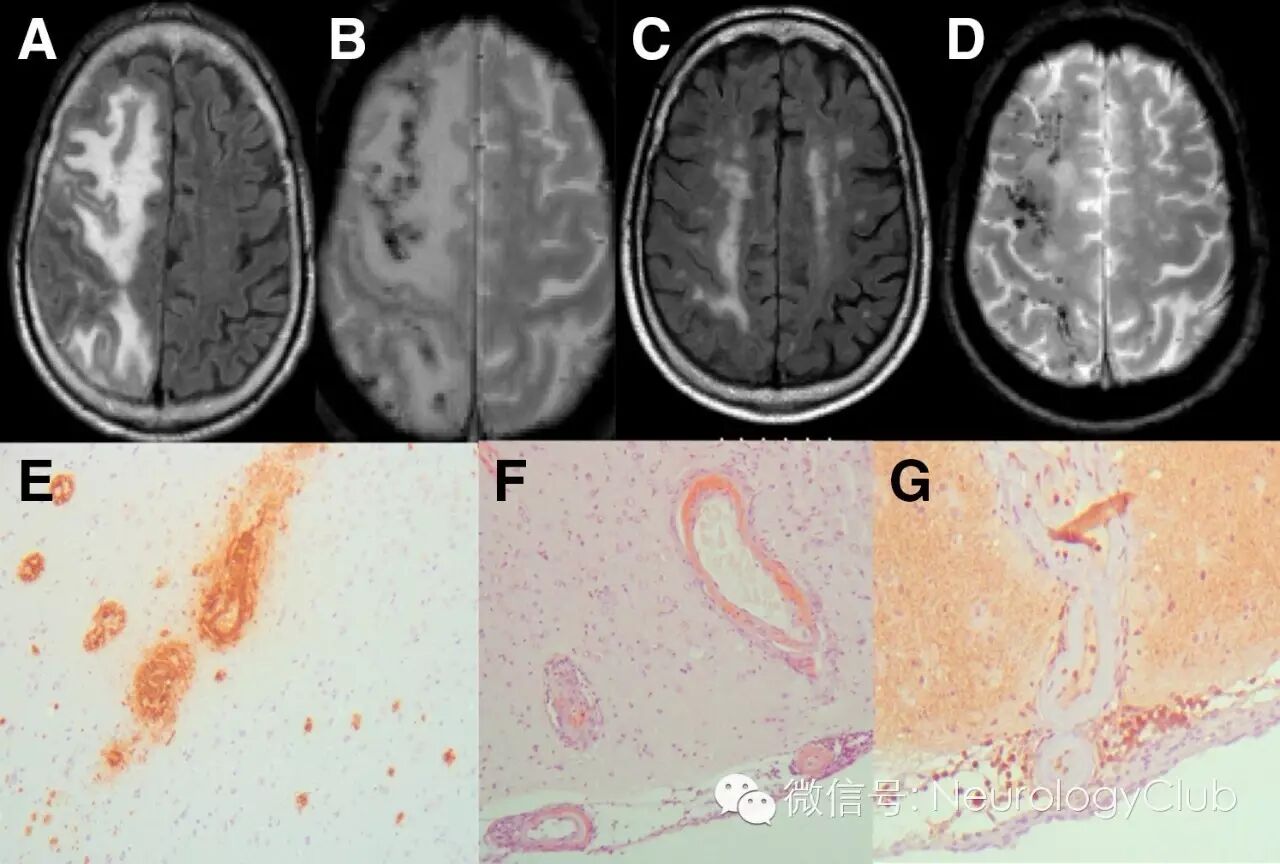

(A-B:FLAIR和T2*WI提示对称性后部颞枕区血管源性水肿伴出血和散在微出血;C-D:第二次入院时的FLAIR和T2*WI提示左侧颞枕区出血;E:柔脑膜和脑实质血管Aβ沉积[刚果红染色,×4];F-G:血管外周淋巴细胞炎性浸润[HE,×20;CD3染色,×10])

A-B:治疗前的FLAIR和T2*WI;C-D:免疫抑制治疗后FLAIR和T2*WI提示病灶明显减少;E-F:脑实质和柔脑膜血管壁淀粉样蛋白沉积[Aβ4染色,×10;刚果红染色,×10];G:柔脑膜血管周围淋巴细胞浸润[CD3染色,×10]

A-B:治疗前的FLAIR和T2*WI;C-D:免疫抑制治疗后1月复查FLAIR和T2*WI提示病灶明显减少;E:脑实质和柔脑膜血管壁淀粉样蛋白沉积[刚果红染色,×10];F:血管壁[箭]和一些淀粉样蛋白斑块[箭头,Aβ4染色,×10];G:淀粉样蛋白沉积的血管周围可见T3淋巴细胞浸润[CD3染色,×40]